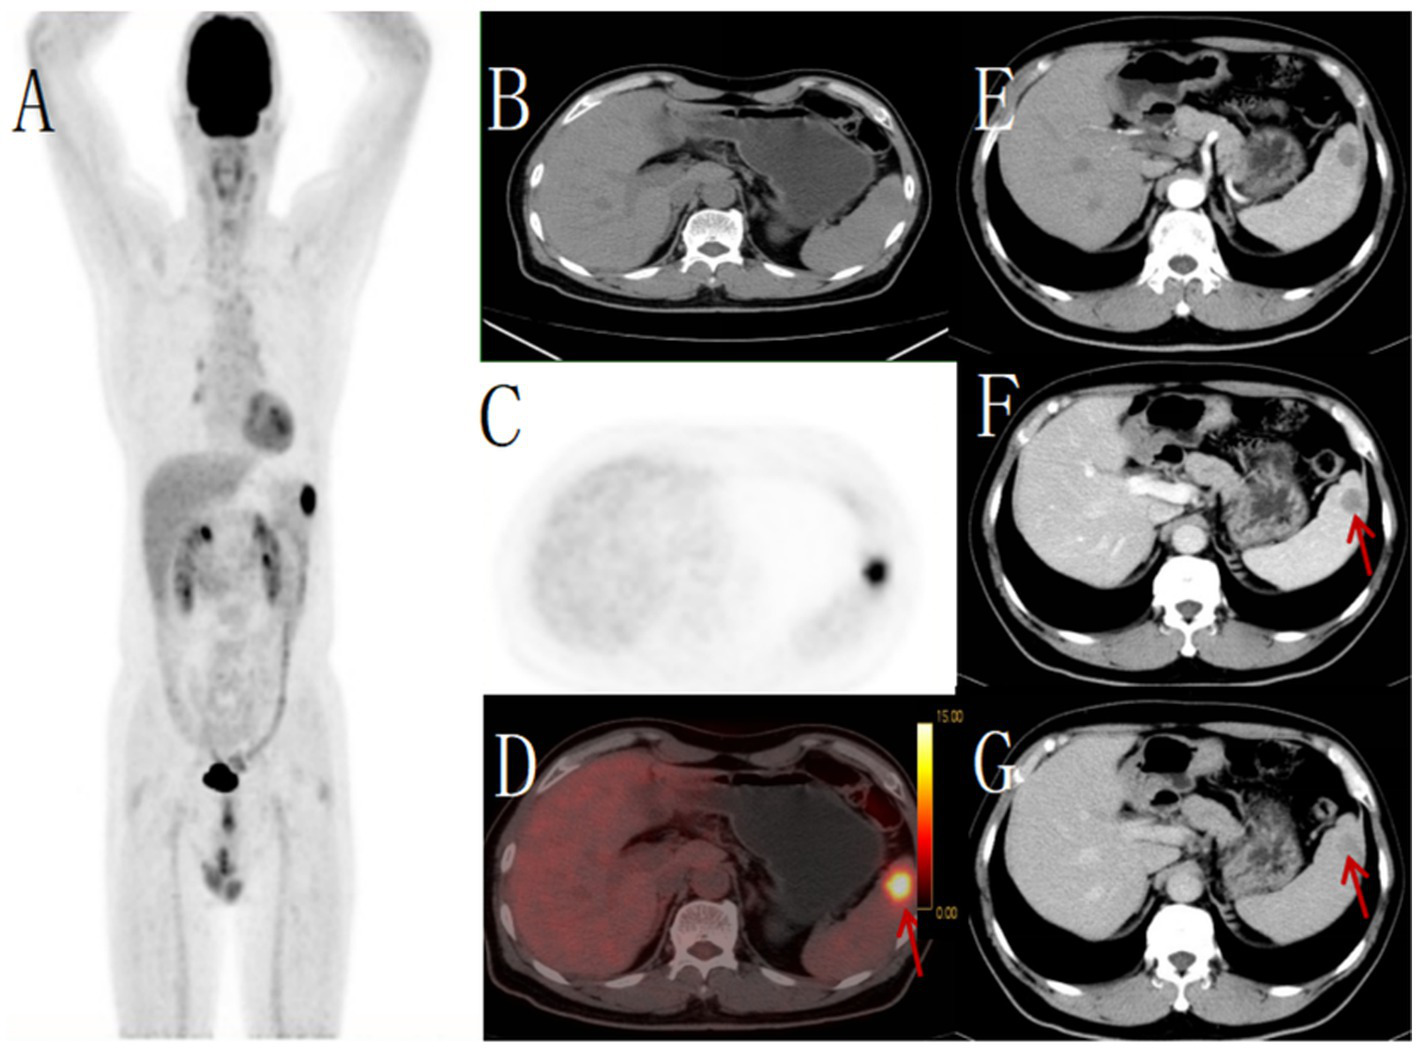

Figure 2

Male, 67 years old, primary splenic angiosarcoma. (A) whole body MIP, (B) axial fusion, (C) coronal fusion, (D) sagittal fusion, (E) enhanced CT-arterial phase, (F) enhanced CT-venous phase, (G) (H-E × 400). 18F-FDGPET/CT showed multiple nodular and massive lesions in the spleen with multiple necrotic areas, PET/CT images showed an abnormal increase in diffuse and uneven uptake of 18F-FDG in the spleen, with a SUVmax of 9.0 (red arrow, B) and no FDG uptake in some necrotic areas (green arrow, C). There were multiple nodular lesions in the liver, the level of FDG metabolism increased, the SUVmax was 5.6 (green arrow, B). Enhanced CT showed diffuse uneven mild enhancement of spleen, and the degree of enhancement increased with time (red arrow, F). Multiple nodular low-density shadows were seen in the liver, which were slightly enhanced by enhanced scan. PET/CT-guided splenic biopsy confirmed the diagnosis of primary splenic angiosarcoma (G).